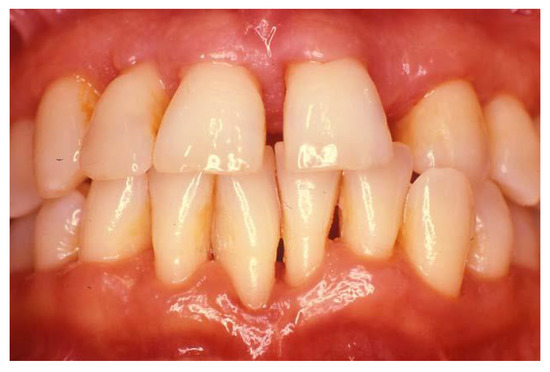

2.2. Necrotizing Periodontal Diseases (NPDs)

2.3. Periodontitis as a Manifestation of Systemic Diseases

2.3.1. Down Syndrome

2.3.2. Human Immunodeficiency Virus (HIV)

2.3.3. Rheumatoid Arthritis (RA)

2.4. Systemic Diseases or Conditions Affecting the Periodontal Supporting Tissues